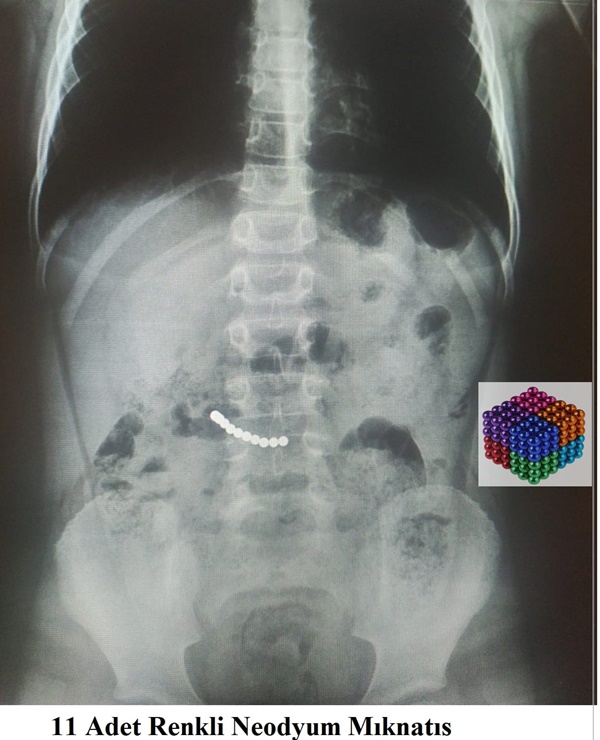

Karın ağrısı şikayetiyle Muğla Eğitim ve Araştırma Hastanesine başvuran 7 yaşındaki U.K'nın kontrollerinde midesinde mıknatıs olduğu belirlendi. Yaklaşık iki saat süren operasyonla çocuğun midesindeki 11 mıknatıs çıkarıldı.

Ekibiyle operasyonu gerçekleştiren hastanenin Çocuk Cerrahisi Ana Bilim Dalı Öğretim üyesi Prof. Dr. Süleyman Cüneyt Karakuş, bazı çocuklarda bu durumun ölümlere kadar giden sonuçlar doğurabileceğini belirterek, "Bazen küçük şeyler çocukların dikkatini çekebiliyor. Hastamızda mıknatısların midede yer değiştirmemesi, ameliyat kararı vermemizde etkili oldu." ifadesini kullandı.